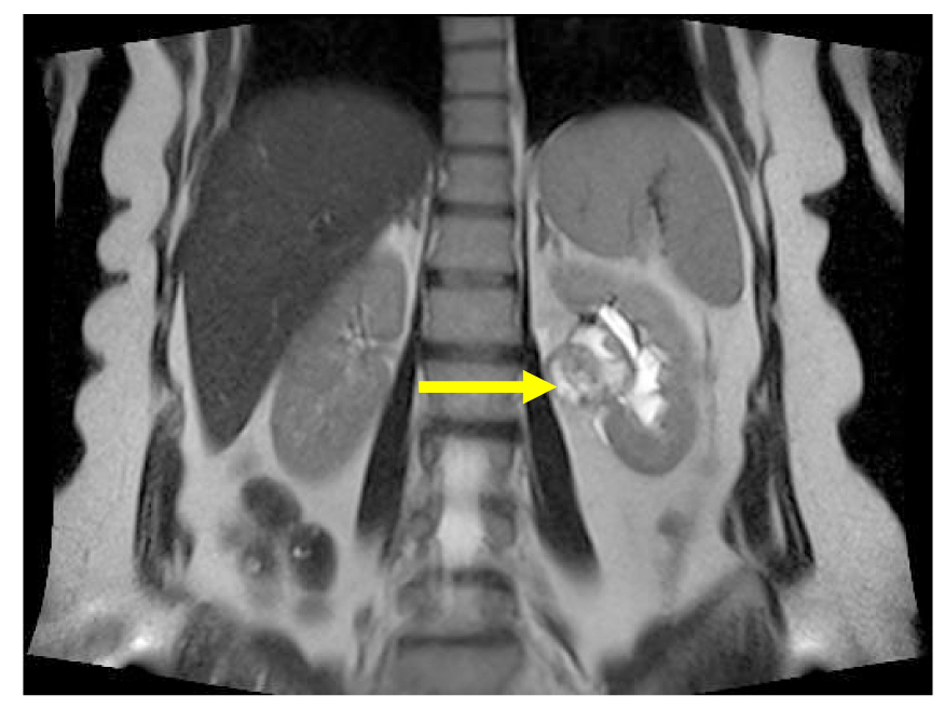

A 51 years old man presented with flank pain and nausea being present over the last 4 months. The biochemical analyses were as follows: AST and ALT normal, FBG: 123 mg/dL; TSH: 0.713 mIU/mL, creatinine: 0.75 mg/dL, urea 26 mg/dL, hemoglobin 13.3 g/dL, WBC: 4,100/mm3, hematocrit: 38.7%, platelets: 230,000/mm3. Physical examination was unremarkable. Medical history of the patient revealed hypertension, diabetes mellitus and hypothyroidism. Renal ultrasound (US) examination revealed hyperechogenic solid mass which was 70 × 58 × 66 mm in size on the left renal pelvis. On MRI examination, grade II hydronephrosis was found on the left kidney and a mass lesion of 78 × 58 × 68 mm was found on the renal hilus which was hypointense on the T1-weighted images and hyperintense on the T2-weighted images and invading the renal pelvis (Fig. 1, 2). Apparent contrast enhancement was observed. The surrenal gland was normal in appearance. There was no lymph node on the para-aortic area. The patient underwent left transperitoneal radical nephrectomy.

![]() Click for large image | Figure 1. Magnetic resonance imaging: mass in pelvis renalis of left kidney (arrow), the coronal reconstruction shows. |